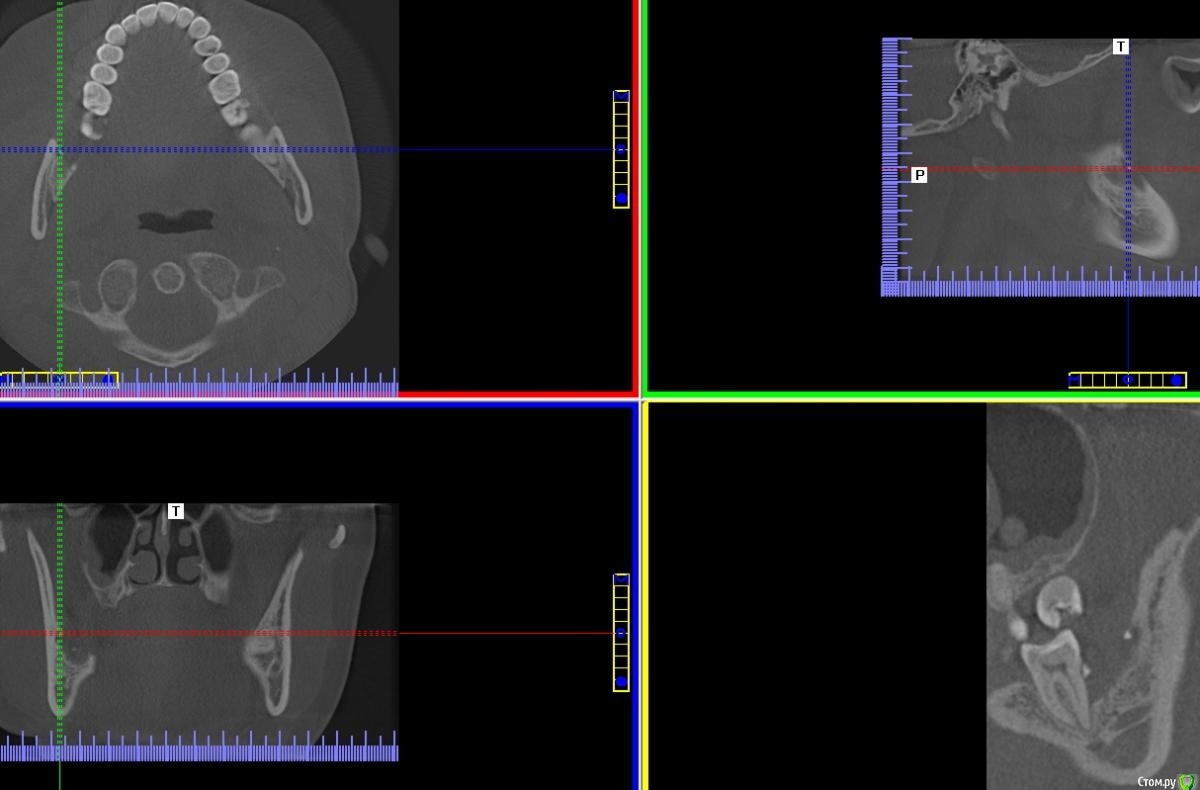

Спилка Опубликовано 15 октября, 2020 Поделиться Опубликовано 15 октября, 2020 В августе решилась на удаление нижних зубов мудрости (38 и 48). Врач - стоматолог-хирург посоветовала не удалять сразу оба, а по-очереди и начать с 48 зуба, ретинированного, дистопированного, возле которого больший очаг воспаления.В процессе удаления был сделан укол анестезии, потом разрезана десна, отпилена коронка зуба, упиравшаяся в соседнюю “семерку” - 47 зуб, и удалён корень, далее рана была зашита. В день операции прицельных снимков ни до, ни после не делали, врач руководствовалась КТ месячной давности, лунка после удаления не промывалась, лекарство, дренаж не ставились.Процесс удаления зуба прошел, на мой взгляд, быстро, дёргано, врач сразу же ушла после завершения, была не в настроении, явно чем-то обеспокоена. На свой счет я это не приняла, но осадок остался.Назначения врача в плане приема таблеток: нимесил, супрастин, амоксиклав, холод первые суткиАнтибиотик, в отличие от прочих назначений, был рекомендован при наличии болей на третий день после удаления.Меня предупредили, что операция сложная, “помучаюсь” с заживлением и восстановлением.Дома первые сутки прикладывала холод, пила нимесил и супрастин по нормам назначения.На третьи сутки супруг заметил, что изо рта стало “плохо пахнуть”, “гнилостно”, позвонил врачу, она сказала, что на третий день отёк самый большой, это норма, и посоветовала начать пить антибиотик, и если будет так же или лучше, все ок, если хуже - приехать на приём, лунку вскроют, заново сформируют сгусток и зашьют.На четвертые сутки после удаления ситуация ухудшилась, было принято решение показаться в областную клинику хирургу. В приемном отделении, увидев мою щеку, погоняли по кабинетам, взяли анализы, сделали рентген, КТ, ЭКГ, еще что-то - уже не помню, и …..поставили диагноз - флегмона околочелюстной области справа. И экстренно прооперировали. Подробности описывать не буду, жутко все это, никому не пожелаю... 11 дней в стационаре, выписали с открытой раной на амбулаторное лечение к хирургу по месту жительства.Я всю жизнь по стоматологам, много разных сменила, читаю информацию, что-то понимаю, но все же я не специалист. Эта клиника самая лучшая и дорогая в области, думала уж там все будет отлично. Но пока лечилась в областном стационаре, много читала и возникли сомнения, что удаление произведено отлично.После того, как рана затянулась, попытались прояснить этот вопрос с клиникой, где удаляли зуб. Там сказали, что я не добросовестный пациент, что никаких установленных нормативов, протоколов лечения не существует, соответственно, врач ничего не мог нарушить при проведении операции по удалению 48 зуба, попугали стоимостью экспертизы. И вообще, после вмешательства врачей областной клиники уже доказать ничего нельзя, засомневались в верности диагноза - флегмона околочелюстной области справа. По мнению директора клиники и глав врача удаление проведено идеально - они смотрели записи камеры наблюдения.Собственно - вопрос в чем - может они правы и удаление действительно прошло “идеально” - как они утверждают, и флегмоны не было.У меня есть 3Д снимки за месяц до удаления и через полтора месяца после. Как могла в программе выставила диапазоны, сделала снимки экрана. И кажется мне, что там осколки зуба в лунке… Муж сделал фото лунки - по-моему осколок видно.Я в растерянности, если клиника отработала идеально, почему такие катастрофические последствия?!! Если так можно - оцените ситуацию в целом, так как теряюсь сформулировать какой-то конкретный вопрос. Заранее спасибо всем! Ссылка на комментарий

Спилка Опубликовано 15 октября, 2020 Автор Поделиться Опубликовано 15 октября, 2020 Загрузите кт на файлообменникhttps://yadi.sk/d/cU-dxQlKtbsNfQКЛКТ И фото места где был зуб Ссылка на комментарий

Irouil Опубликовано 16 октября, 2020 Поделиться Опубликовано 16 октября, 2020 Вот именно мнение клиницистов меня и интересует, насколько правильно меня лечилиИменно это сказать клиницист не может в принципе, такие заключения даются на экспертизе врачом-экспертомКакой результат по вашему достигнут в стационаре, не подохла?Я бы выразился иначе, но суть Вы передали верно: главная цель лечения пациентов в экстренной медицине (а инфекционные воспалительные процессы, в первую очередь флегмоны, в челюстно-лицевой области являются показанием именно для применения такого вида лечения) - спасение жизни, ибо угроза для нее была. Теперь по существу Во-первых я не вижу на предоставленной компьютерной томограмме потенциально инфицированных фрагментов, угрожающих Вашему здоровью. И расскажите подробнее про губу - отмечается ее онемение? Сможете обрисовать карандашом область онемения и сделать фото? Ссылка на комментарий

Zlata-doctor Опубликовано 17 октября, 2020 Поделиться Опубликовано 17 октября, 2020 (изменено) Я не вижу никаких осколков на представленных снимках. Замечу, даже если бы они там и были, это не может являться причиной флегмоны. Патофизиология данного процесса гораздо более сложна и связана также с особенностями флоры вашей полости рта, вашего иммунитета, с непростой анатомией данной области, сложностью удаления и другими факторами. И таки да, околочелюстной области как анатомического образования, не существует. Промывание, введение лексредств и дренирование проводятся врачом по показаниям, он не должен 100% это сделать, а иногда это и нежелательно. Также хочу Вам сказать, что здесь собрались врачи, которые абсолютно бесплатно в рамках своей компетенции пытаются помогать вам, пациентам. И никакая это не цеховая солидарность, просто проводить экспертизу и ставить вердикт на расстоянии, не имея полной задокументированной истории вашей болезни-непрофессионально, преступно и аморально. К сожалению, люди сейчас воспитаны на скандальных ТВ роликах, где диагнозы обвинения, а заодно и приговор раздаются на раз-два. Здесь такого горлопанства в погоне за сенсацией не будет. Мы вам очень сочувствуем и желаем скорейшего выздоровления. Изменено 17 октября, 2020 пользователем Zlata-doctor 5 Ссылка на комментарий